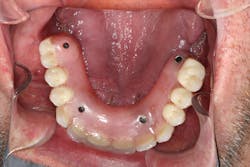

- An implant-supported overdenture or—more easily understood by many patients—a “snap-on” denture, which utilizes implants as anchors (figure 3).